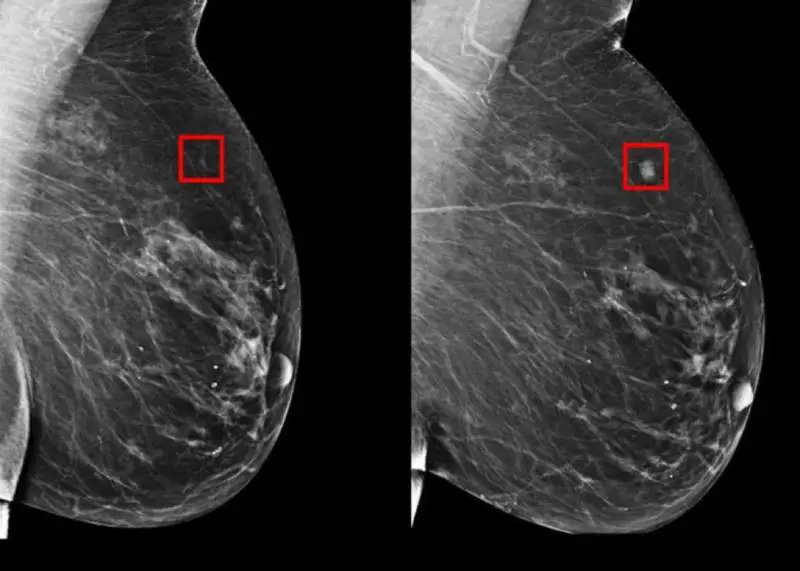

Entrando nel dettaglio, grazie un algoritmo chiamato "Image encoder" nella prima fase dello screening si acquisiscono le immagini delle mammografie mediante i raggi X: a questo punto lo strumento assorbe i dati e analizza molto scrupolosamente i risultati. Subito dopo, grazie all'intelligenza artificiale, queste immagini vengono integrate con numerose scansioni digitali così da avere un quadro più completo e una serie incredibile di dati che l'uomo, da solo, farebbe fatica a tenere. Con il mix di informazioni il nuovo strumento è molto preciso nella previsione di tumore al seno per la paziente in un arco di tempo che varia da uno fino a cinque anni.

C'è anche da sottolineare che questo modello riesce a distinguere anche i tessuti dei seni delle pazienti e confrontare quello destro con quello sinistro in modo da identificare eventuali differenze che possono suonare come un campanello d'allarme e attuare tutte le prevenzioni del caso.

"Possiamo, con sorprendente precisione, prevedere se una donna svilupperà il cancro nei prossimi 1-5 anni basandoci esclusivamente sulle differenze localizzate tra il tessuto del seno sinistro e destro", hanno concluso i ricercatori.